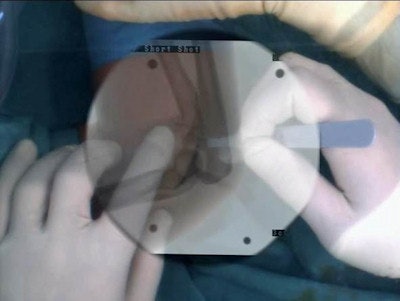

In addition, Navab pointed to the Narvis project CamC, currently used in the trauma unit of Klinikum Innenstadt at the Munich University Medical Center for orthopedic and trauma surgery. CamC is a conventional mobile C-arm equipped with a camera and a system of mirrors so that coregistration of the optical view and the x-ray image provides the surgeon with a "see-through" vision of bone beneath skin. This allows maximum intraoperative information at minimum radiation exposure to patients and medical staff.

So far, 40 patients have been treated using CamC technology, but it will be rolled out to three Munich hospitals in October for patient studies. Although mainly of interest to surgeons at present, further use of CamC for catheter placement may be envisaged in future.